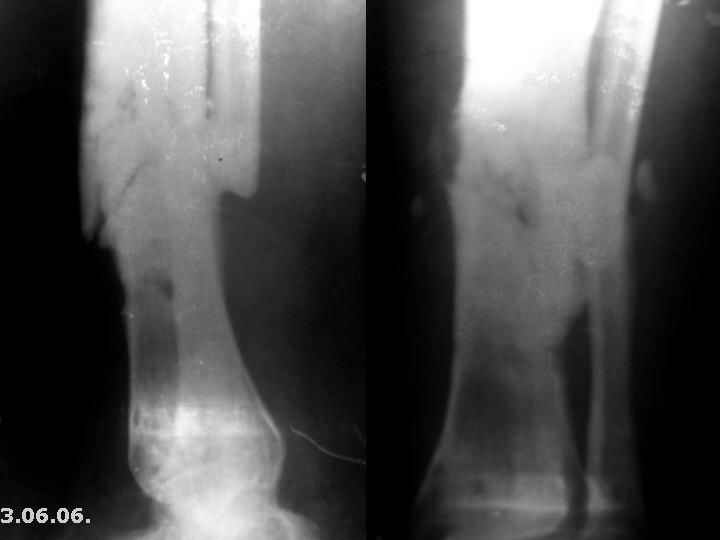

Мужчина, 29 лет. Состоит на лечении в ЦРБ.Диагноз: Замедленно сростающийся со смещением повторный перелом обеих костей левой голени вс/3-н/3, состояние после ВЧКО, хронический остеомиелит костей левой голени, свищевая форма,трофический синдром, смешанная контрактура левого коленного, голеностопного суставов.

Травма 20.12.04. - открытый 2Б тип, оскольчатый перелом обеих костей левой голени в с/3-н/3 сосмещением отломков (ДТП). 20.12.04.- ВЧКО костей голени АВФ спице-стержневого типа, ПХО ран.Лечился амбулаторно. Перелом длительно не сростался. АВФ демонтирован 22.06.05., разрешена нагрузка на ногу, после чего появилась подвижность в области перелома. 8.07.05. - ВЧКО, туннелизация по Беку. Течение осложнилось развитием спицевого остеомиелита, 1.11.05. АВФ демонтирован, получал консервативное лечение. После нормализации состояния 17.11.05.- секвестрэктомия, ВЧКО голени.12.04.06. АВФ демонтирован.

3.06.06.повторная травма - закрытый повторный перелом левой б/б кости в с/-н/3, лечился методомгипсовой иммобилизации.

Место болезни - ось голени искривлена. Kеллоидные рубцы в местах проведения спиц, по передней поверхности голени. По передней и внутренне-боковой поверхности голени в определяется 3 свища с умеренным серозным отделяемым. Отек голени и сустава, движения в коленном и голеностопном суставах ограничены, неврологических расстройств в стопе нет.